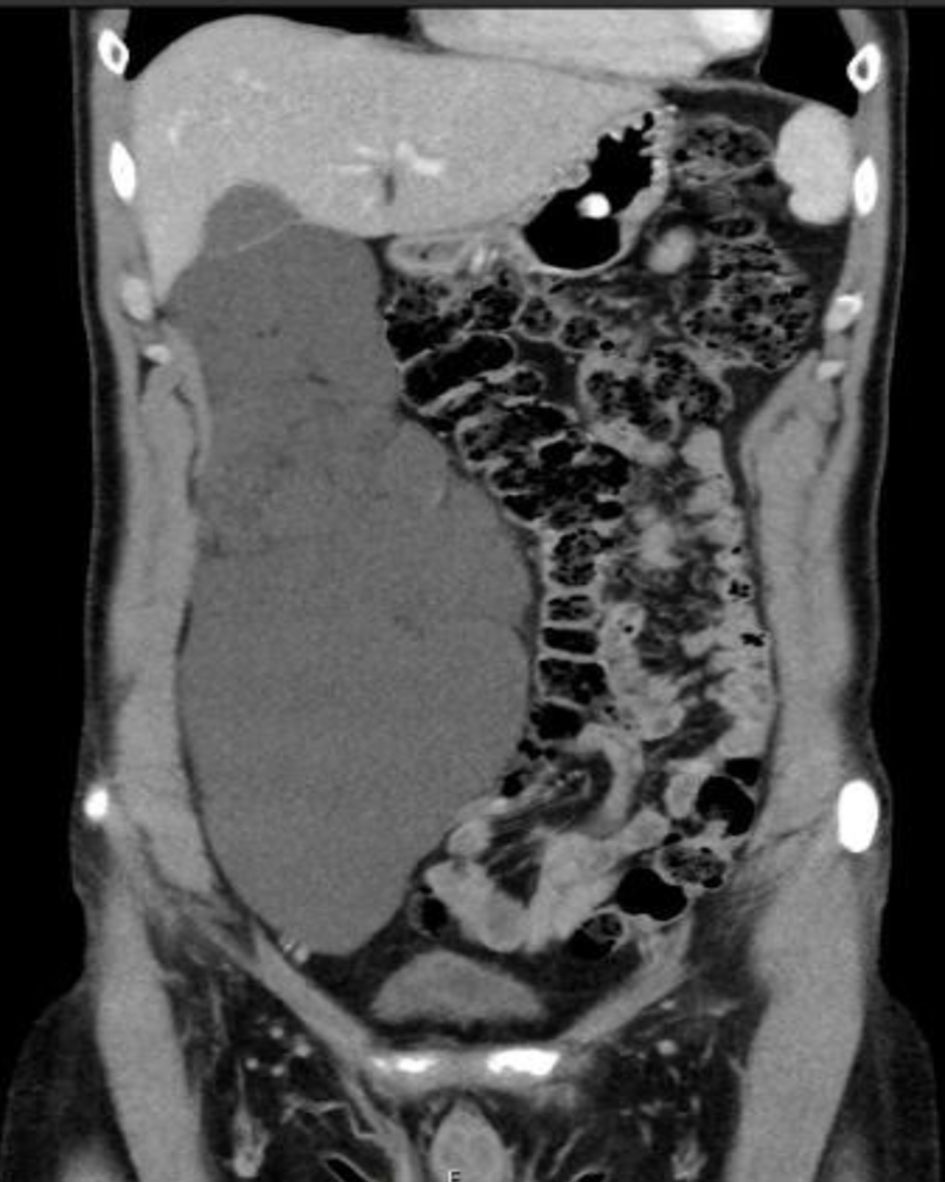

Imaging tests, including US, CT scan and MRI, are crucial for the workup diagnosis of primary ARL. Radiological tests can determine the precise size and exact site of the primary tumor, presence/absence of septations and locularity, and the relationship to nearby organs (whether it causes mass effect on nearby structures) as well. Moreover, imaging exams can rule out other retroperitoneal cystic lesions originating from the kidneys, pancreas or liver [28]. Abdominal MRI has been considered the imaging modality of choice for the diagnosis of ARL [25]. This contradicts our results, as abdomino-pelvic CT scan was undoubtedly the most commonly used modality for diagnosis, reported in 76 out of 80 patients. On the other hand, MRI has been part of the workup in only 26 patients. All patients who underwent MRI were also subjected to other testing modalities, mainly abdomino-pelvic CT. Radiological findings of the different imaging tests are usually identical and include thin-walled, multiseptated, multilocular retroperitoneal cystic lesion [29]. This is similar to the results of this review, as the majority of patients displayed multilocular, multiseptated cystic mass (Fig. 1). In the majority of primary ARL cases, the tumor was located in the right retroperitoneal cavity, followed by the left and mid retroperitoneal space. Calcification of the cystic tumor is an extremely rare radiological finding, reported only in a single case [15]. Primary ARL, as have been mentioned, is characterized by a wide range of tumor dimensions (4 - 30 cm). The mean diameter for ARL was 11 cm. In distinct cases of ARL, when the tumor is centrally located in the retroperitoneum, especially retropancreatic, EUS can aid in the differentiation between true pancreatic cyst and primary retroperitoneal cyst [16].

![]() Click for large image | Figure 1. An abdomino-pelvic CT scan (coronal plane) showing a large septated, multiloculated right retroperitoneal cystic mass, displacing the right colon medially. CT: computed tomography. |